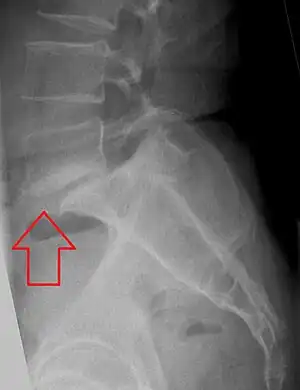

X-ray of measurement of spondylolisthesis at the lumbosacral joint, being 25% in this example. -

Plain radiography is often the first step in medical imaging.[13] Anteroposterior (front-back) and lateral (side) images are used to allow the physician to view the spine at multiple angles.[13] Oblique view are no longer recommended.[24][25] In evaluating for spondylolithesis, plain radiographs provide information on the positioning and structural integrity of the spine. Therefore, if further detail is needed a physician may request advanced imaging.